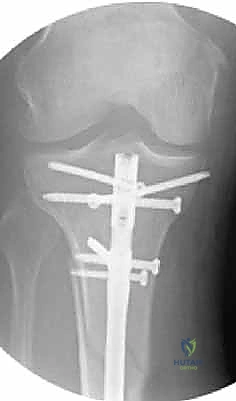

- التثبيت التشابكي (Interlocking): يتم تمرير مسامير صغيرة عرضية عبر العظم والمسمار النخاعي في الطرفين العلوي والسفلي، مما يمنع دوران العظم حول المسمار ويحافظ على طول الساق الطبيعي بدقة متناهية.

4. إدخال المسمار النخاعي والتثبيت النهائي

يتم تمرير مسمار التيتانيوم بدقة داخل العظم. وبمجرد التأكد من موضعه المثالي بالأشعة، يقوم البروفيسور هطيف بإدخال المسامير التشابكية (Locking Screws) العرضية في أعلى وأسفل المسمار لضمان التثبيت المطلق.